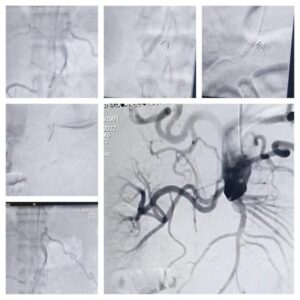

La Rioja. APOS autorizó la primera intervención híbrida realizada en la provincia a un paciente con síndrome de Leriche

El procedimiento fue realizado por un equipo de profesionales del INCOR conformado por los Dres. [...]